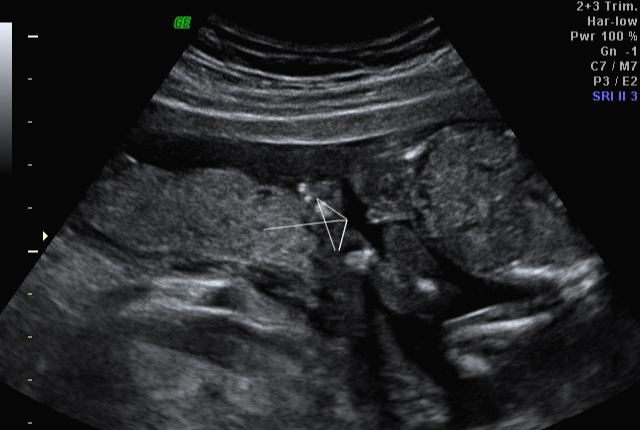

한 달 뒤인 17차 때 다시 사설로 가서 초음파 검사를 받았는데 검사해주시는 분 께서 한참을 보시더라고요~ 그러면서 어떻게 보면 딸 같다고 하셔서... 응? 100프로 아들이라 해서... 다 아들껄로 준비하고 있는데.. 무슨 소리지? 하고 다시 한번 봐달라고 하니 아들이라 하시면서 위에 초음파를 보여주셨어요!

위에 아들이라 했던 초음파 사진은 다 딸 초음파 사진이니 성별이 궁금하신 분들은 딸 초음파 사진으로 참고해서 보시면 좋을 것 같아요~그리고 전 결혼 5년 만에 가진 첫 아이라 설레는 마음에 너무 이르게 아이 용품들을 준비했는데 출산 2~3달 전에 준비해도 늦지 않은 것 같아요~ 혹시 저처럼 성별 반전이 있을 수 도 있으니 아이 용품은 천천히 준비하시길~~!